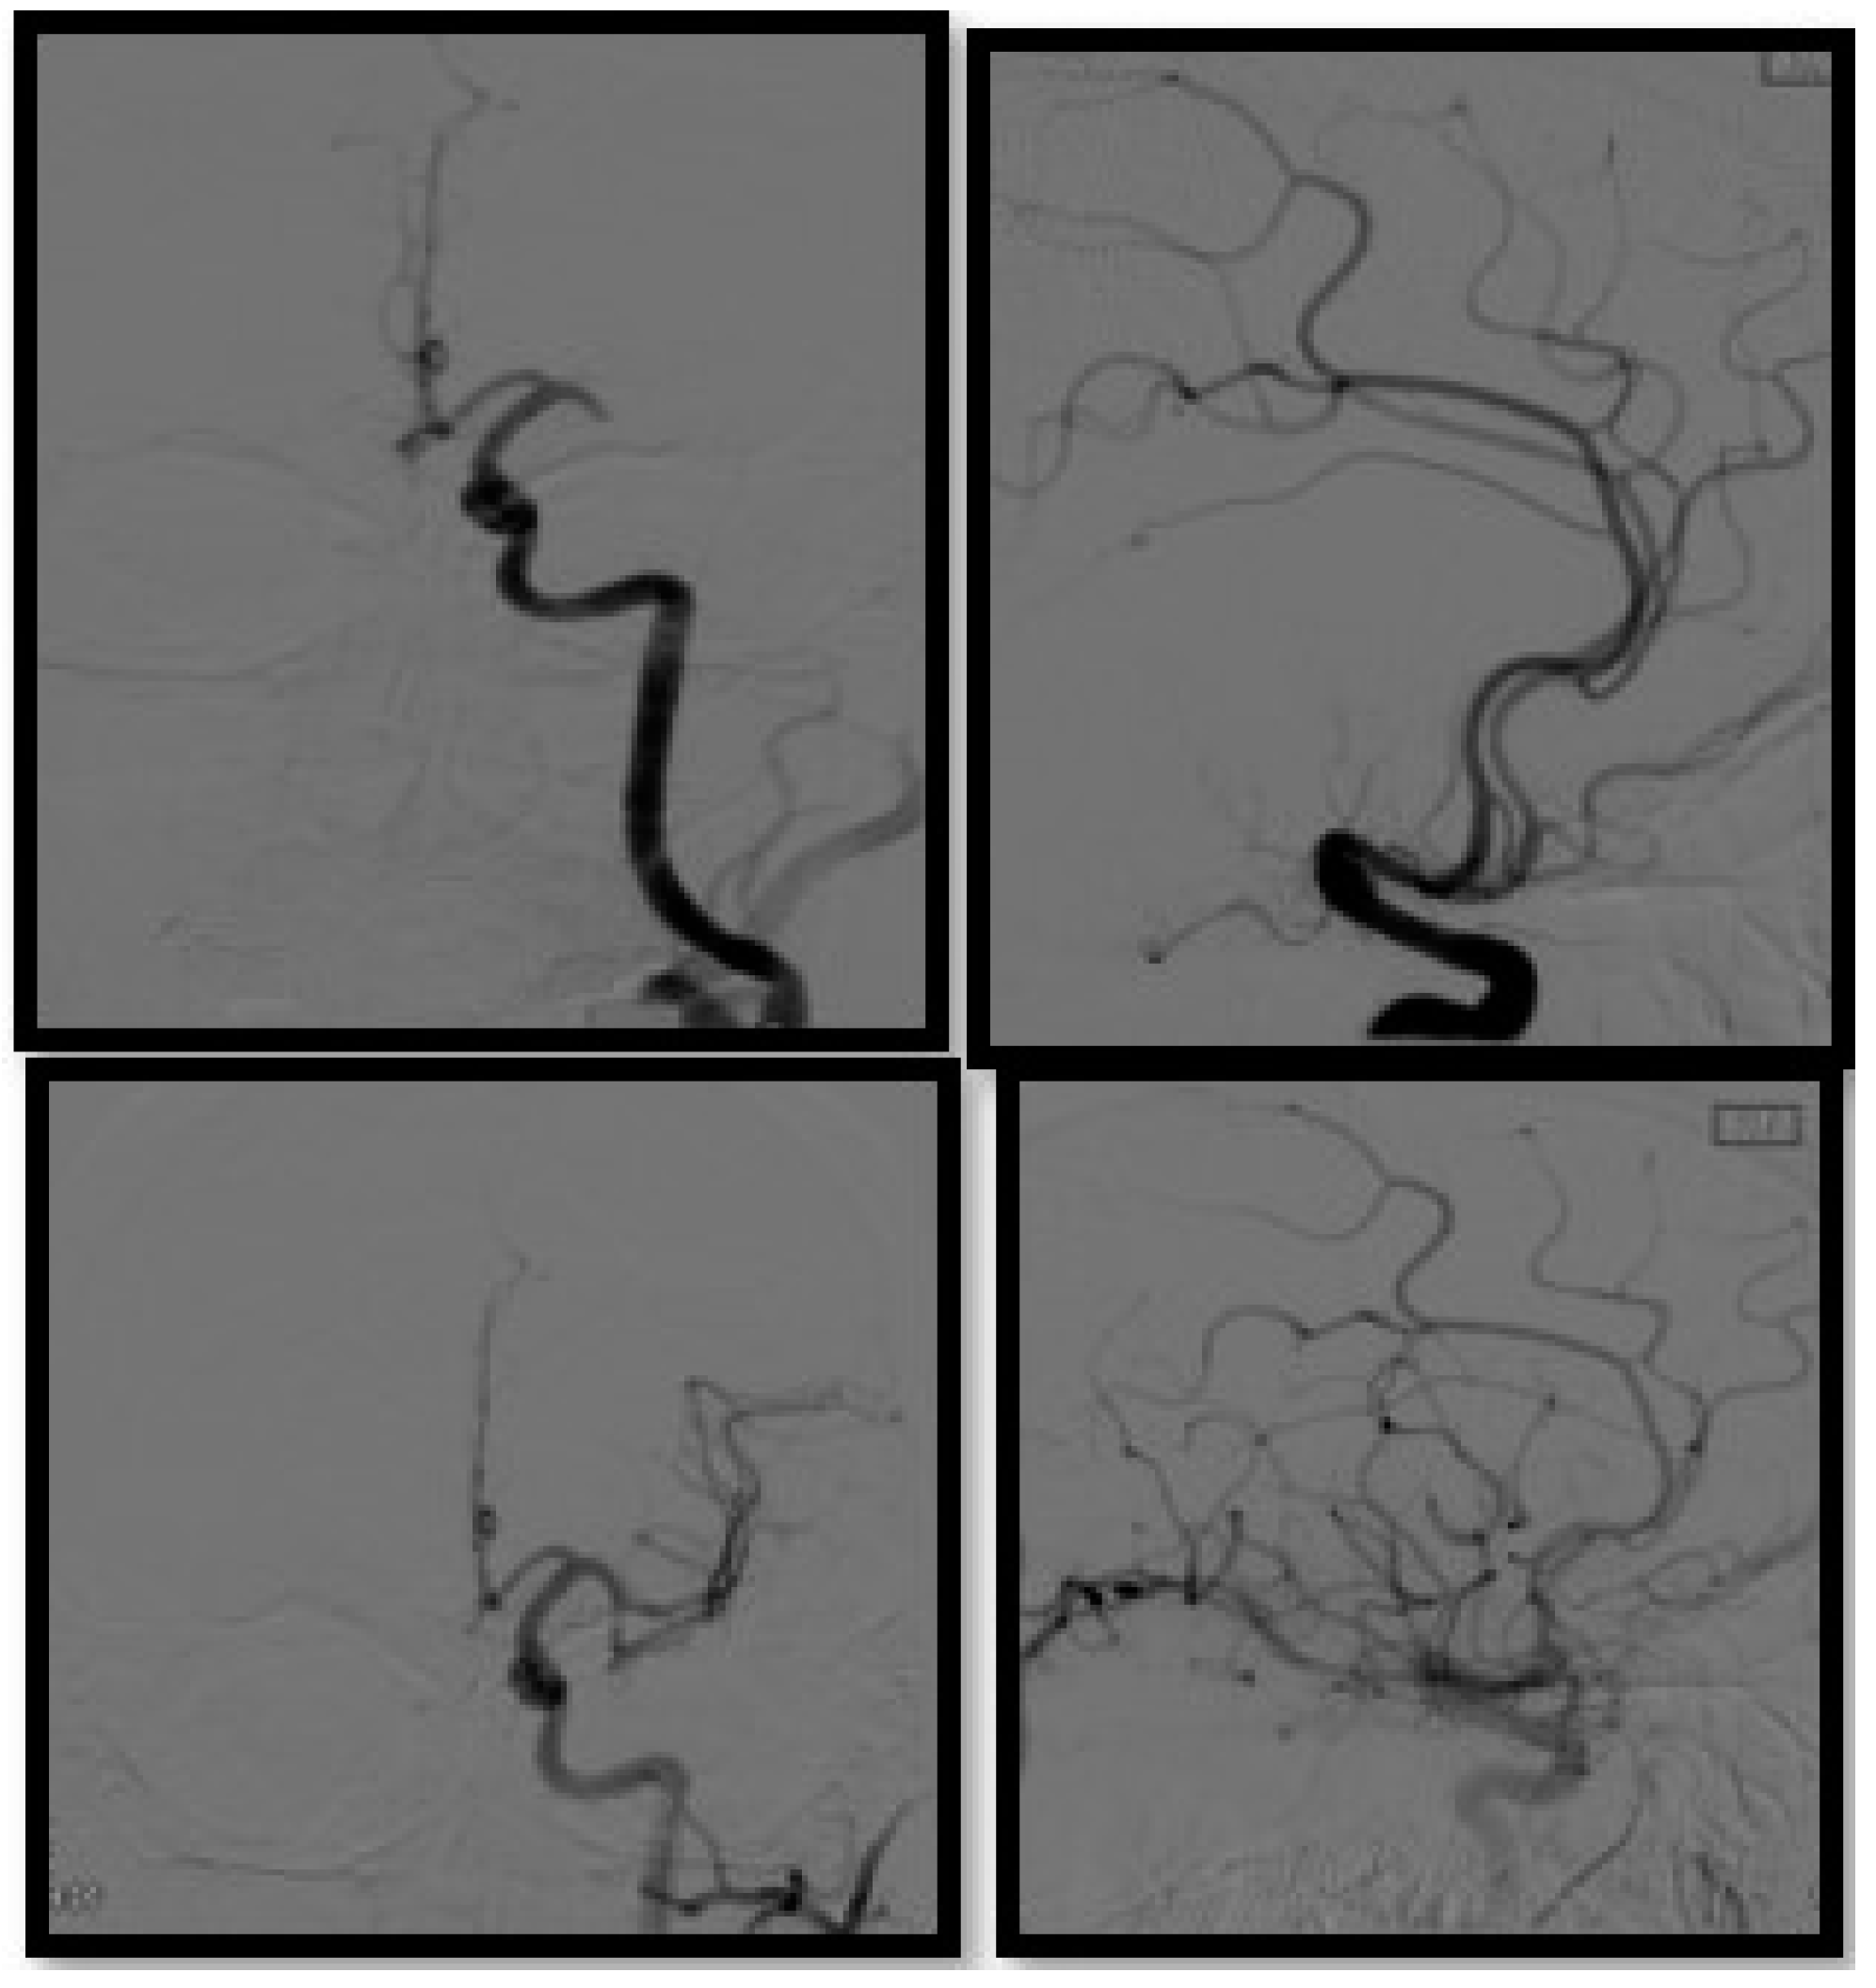

2.5. Evolution of the Concept of the Tissue Window and Late Window Trials